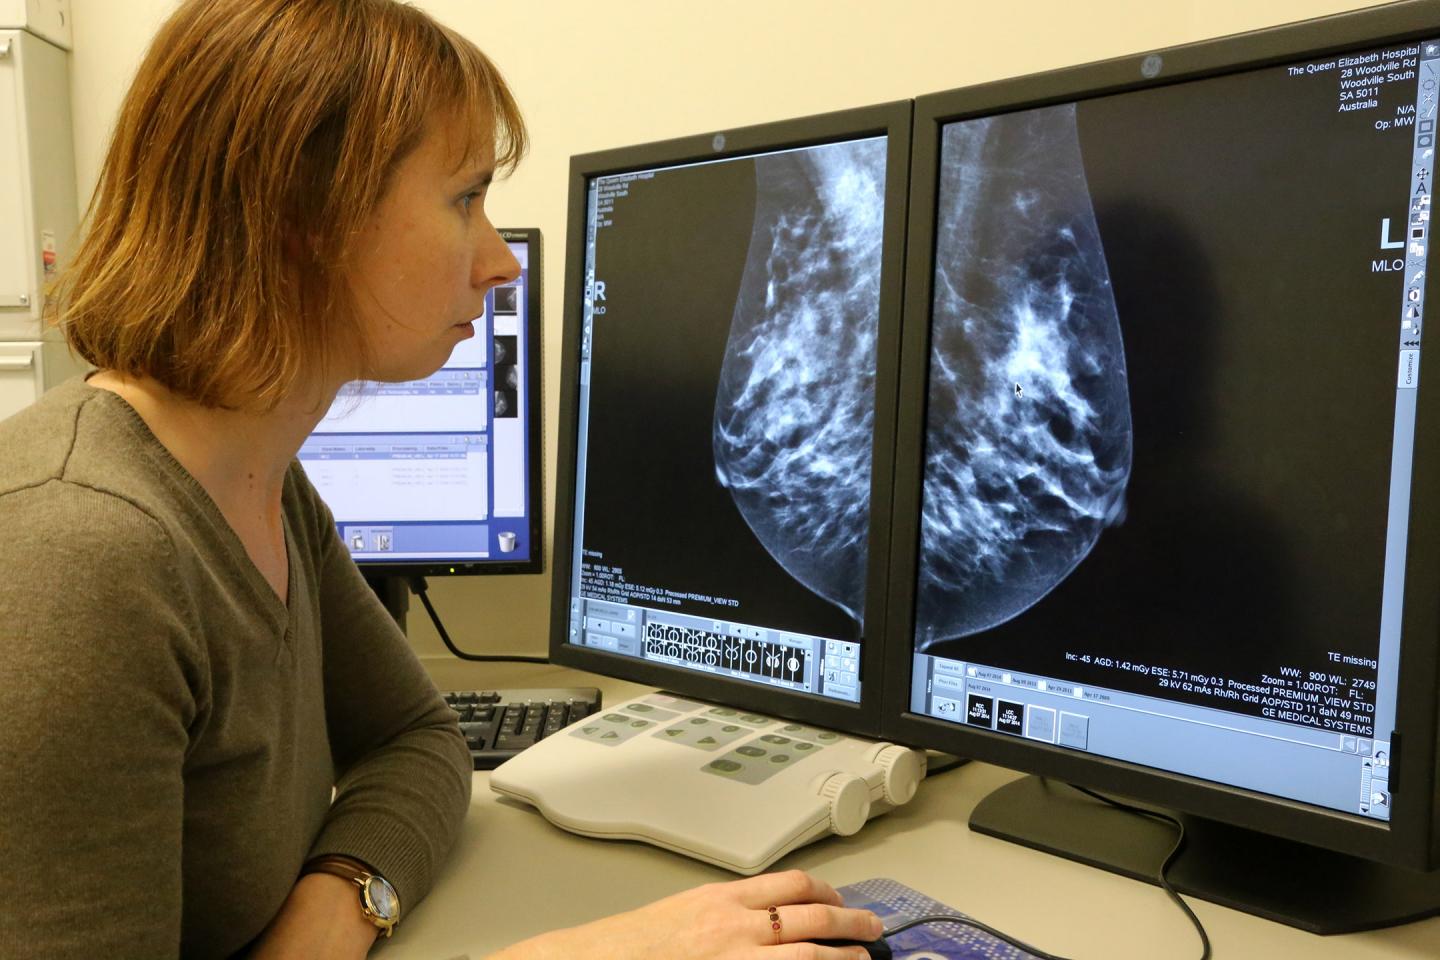

Adelaide researchers are one step closer to breast cancer prevention after finding a new driver for breast density, an identified risk factor for breast cancer.

For the first time, researchers have shown that chronic low-level inflammation drives increased breast density and is associated with a woman's risk of developing breast cancer.

"With this research we believe we may be able to identify the women most at risk of inflammation-associated breast cancer through measuring their breast density and therefore identify those who will most benefit from anti-inflammatory treatment," Associate Professor Ingman said.